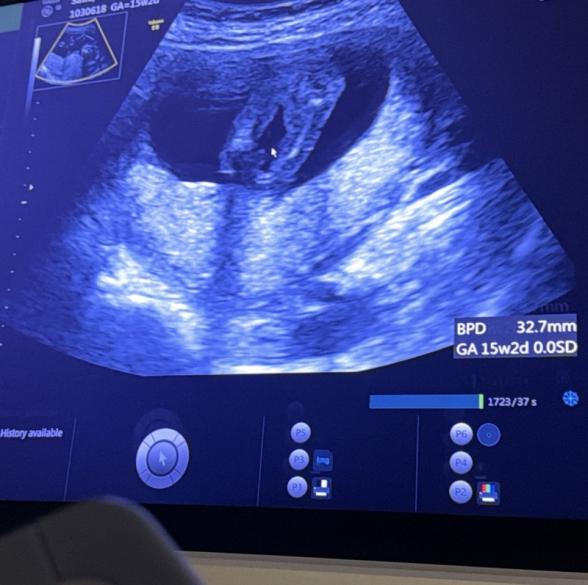

現在15w2dの妊婦です。

1つ目の写真は今お股になにもないように見えますが